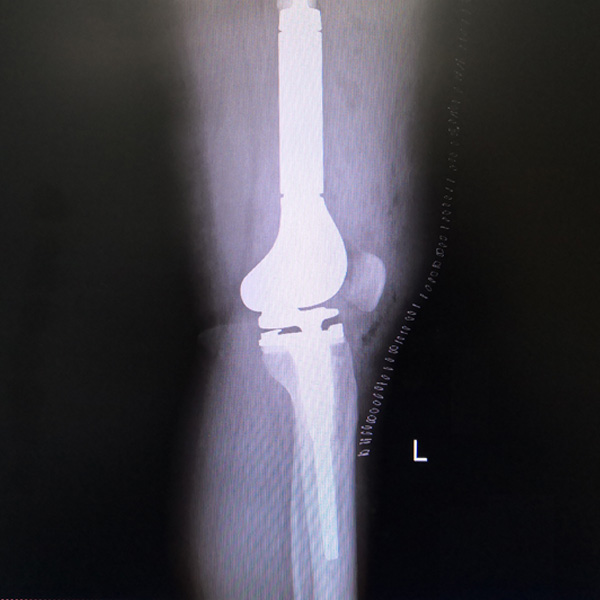

• 骨肉瘤手術骨肉瘤手術手術后手術前

骨肉瘤手術

患者張某,女,14歲,診斷為“左股骨遠端骨肉瘤”,當地醫院因為醫療技術和能力的限制,只能考慮截肢手術。患者家屬通過平臺推薦,指定到哈......